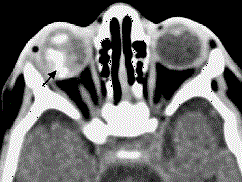

问题 患儿,男性,2岁,足月顺产,无吸氧史。家长发现右眼白瞳症,对光线反应不敏感。超声波提示眼内占位性病变,直径约6mm。无全身性疾病,无眼病家族史。 辅助检查中最有意义的发现是(如图) ( )

选项 A、眼内钙化 B、虹膜红变 C、视网膜脱离 D、眼内压升高 E、眼轴短

答案 A